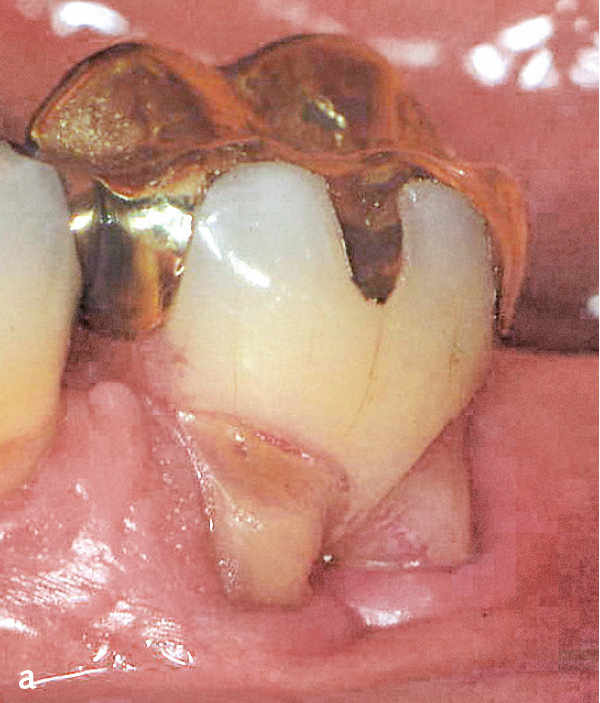

Eines der Charakteristika der parodontalen Destruktion ist ihre Stellenspezifität, d. h. innerhalb einer Dentition bzw. an einem einzelnen Zahn können verschiedene Stadien parodontaler Destruktion auftreten (s. Abb. 1). Dies kann durch die Besiedlung verschiedener parodontaler Taschen mit unterschiedlich virulenten Keimen6 oder durch unterschiedliches Auftreten bzw. Ausprägung lokaler Faktoren bedingt sein. Zu diesen lokalen Faktoren, die die mikroökologischen Verhältnisse in der Mundhöhle beeinflussen und damit Entstehung sowie Progression der Parodontitis begünstigen können, gehören Zahnstellung (Schachtelstellung von Frontzähnen, Mesialkippung von Molaren) und -morphologie. Insbesondere in den Furkationen mehrwurzliger Zähne finden sich anatomische Besonderheiten wie Schmelzparaplasien (Schmelzsporne, -inseln, -tropfen und -perlen) (Abb. 7a), Wurzelzementkämme und blind endende Öffnungen6. Im Bereich der teilweise weit in die Furkation reichenden Schmelzsporne besteht kein bindegewebiges, sondern nur ein epitheliales Attachment. Während das bindegewebige Attachment erst im Stadium der fortgeschrittenen Läsion zerstört wird, geht nach bakterieller Exposition und Entstehung einer Gingivitis das epitheliale Attachment bereits beim Übergang von der frühen zur etablierten Läsion (Gingivitis) verloren. Auch Furchen in der Wurzeloberfläche (z. B. palatinale Furche seitlicher Oberkieferschneidezähne) gehören zu diesen lokalen Kofaktoren der Parodontitis, aber auch iatrogen bedingte Situationen wie überhängende oder subgingival gelegte Restaurationsränder, die die Besiedlung der betroffenen Zahnoberflächen insbesondere mit pathogenen Keimen begünstigen (Abb. 7b)6.

Abb. 7a und b Lokale Parodontitis-Risikofaktoren: a) Zahn 36 nach Tunnelierung mit breitem und weit in den Furkationsfornix reichenden bukkalen Schmelzsporn; b) Panoramaschichtaufnahme einer Frau im Alter von 35 Jahren (1995): Parodontitis, generalisiert Stadium III, Grad C. Der Zahnersatz mit zum Teil stark überhängenden Kronenrändern wurde im Jahr 1994 eingegliedert.